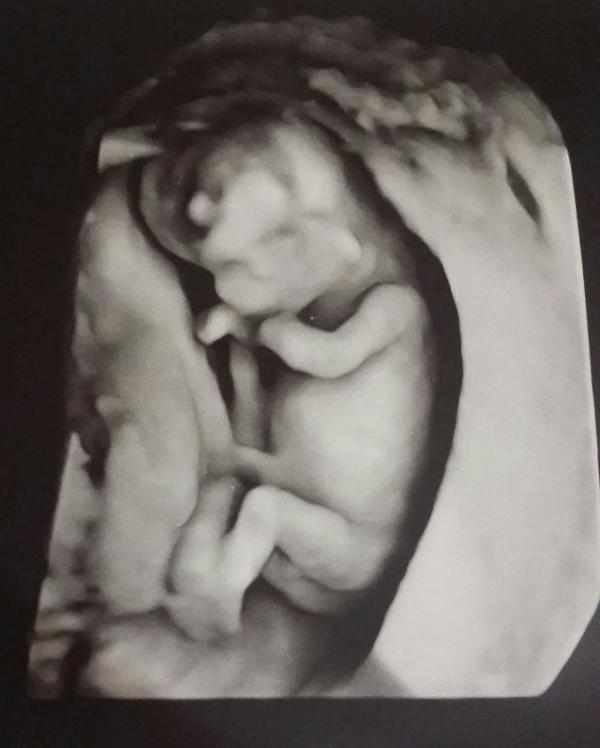

Ура! Сходили на первый скрининг к Титаренко М.В. Увидела малыша❤❤❤ Как это трогательно и мило.. лялечка ножками шевелила, и терла глазки. Сделали 6 снимков. Пол не определили. Но мы так счастливы 💋💋💋 Узист супер!

Лялечка крошечка :) Уже безумно любим и ждем 😢

Как же это мило😍 главное здоровый ребенок 🌼а моя интуиция говорит,что это девочка😄

Здоровья Вам и малышу. Кажется мне что мальчик😉 Подпишусь что бы узнать потом🌷

Это очень эмоционально иитрогательно. :) С мужем но без него :) он с сыном за дверью был. На второй скрининг возьму :)